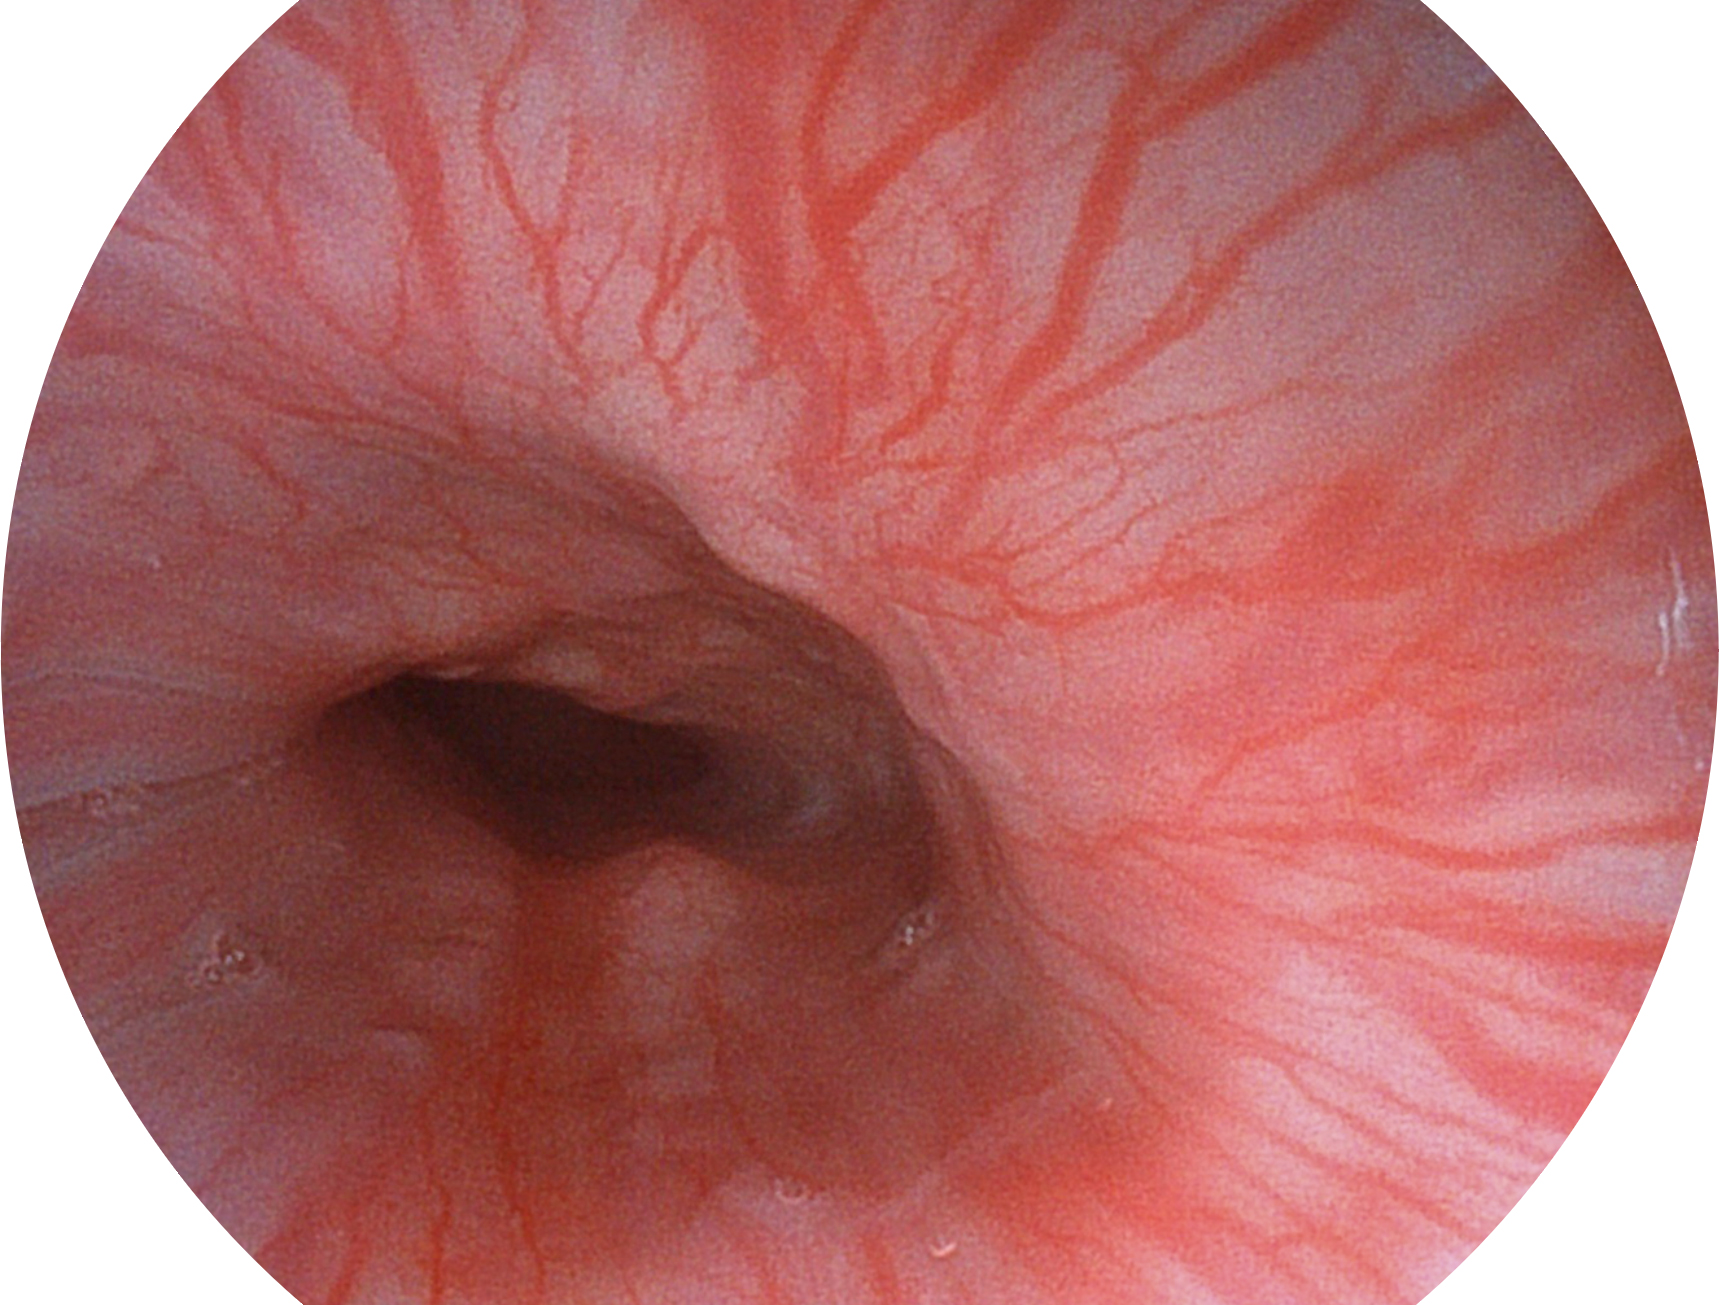

哈哈体育官网新开发的内镜染色技术,主要是基于多波长LED 光源的开发,VLS-55Q 四波长LED 光源是由四个不同颜色的LED光按照相应照明模式所规定的特定发光比例进行合束后形成,合束后形成的照明光的光谱由红光、绿光、蓝光及蓝紫光这四个不同的波段范围构成。具有更高光谱自由度,通过光谱比例的控制,实现了聚谱成像技术,英文全称为“Spectral Focused Imaging, SFI”,缩写为“SFI”和光电复合染色成像技术,英文全称为“Versatile Intelligent Staining Technology, VIST”,缩写为“VIST”。